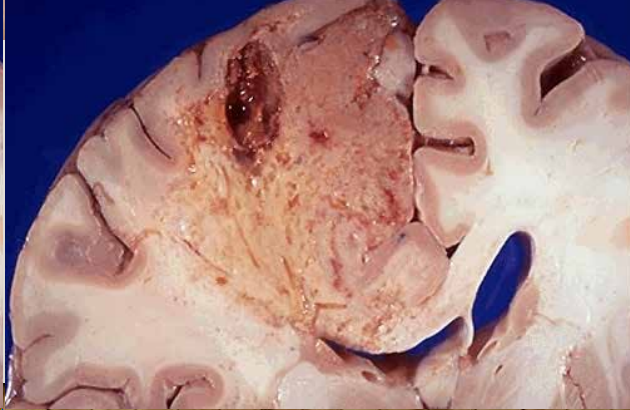

Necrosis por liquefación

Mas información: Necrosis por liquefación, al ser el SNC mayoritariamente grasa, solo se da en este sistema. Se ven cavidades vacias con liquido turbio, a veces purulento. Al microscopio tampoco se distingue el tipo de organo, algo mas rosa claro y restos celulares